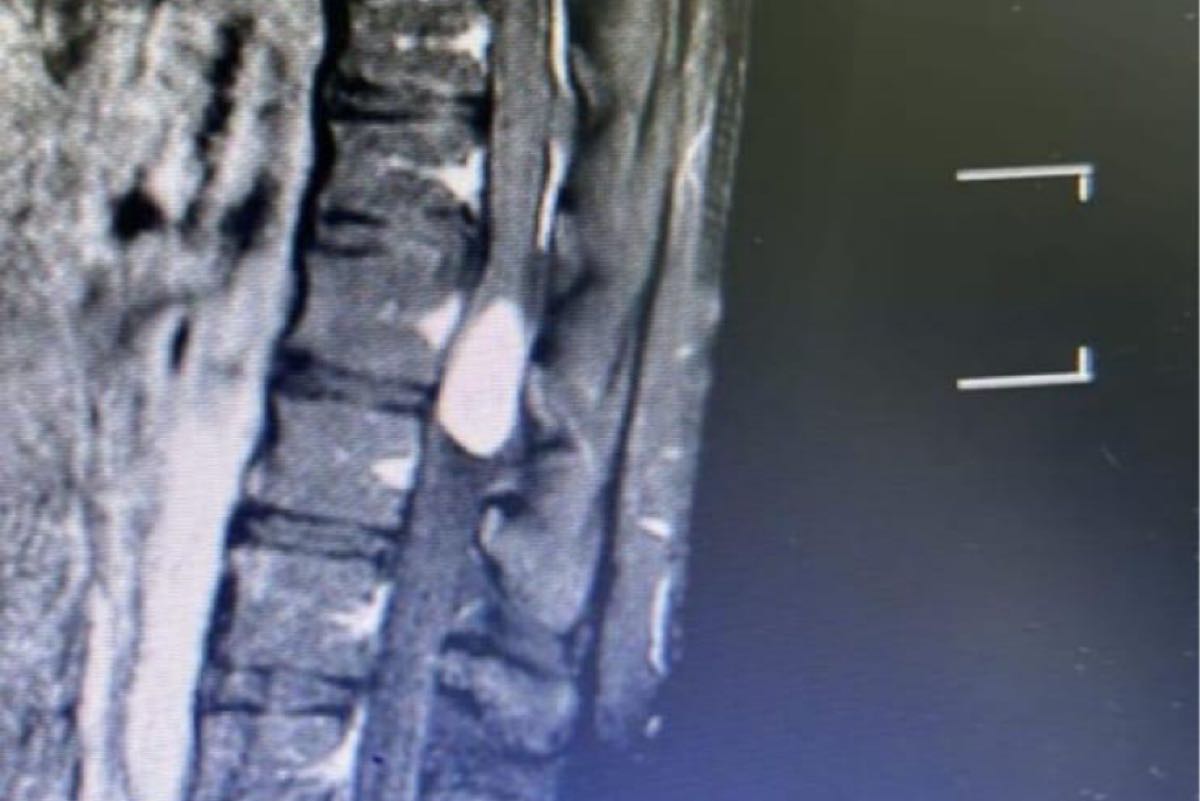

تمكن فريق طبي متخصص من قسم جراحة المخ والأعصاب والعمود الفقري في شبكة القطيف الصحية، من إجراء عملية جراحية دقيقة وناجحة لاستئصال ورم ضمن الحبل الشوكي لشاب في العقد الثاني من العمر.

وأوضح أن الورم الذي تم استئصاله كان يسبب ضغطاً شديداً على الحبل الشوكي، مما يؤثر على حركة الشاب وقدرته على القيام بأنشطته اليومية بشكل طبيعي،